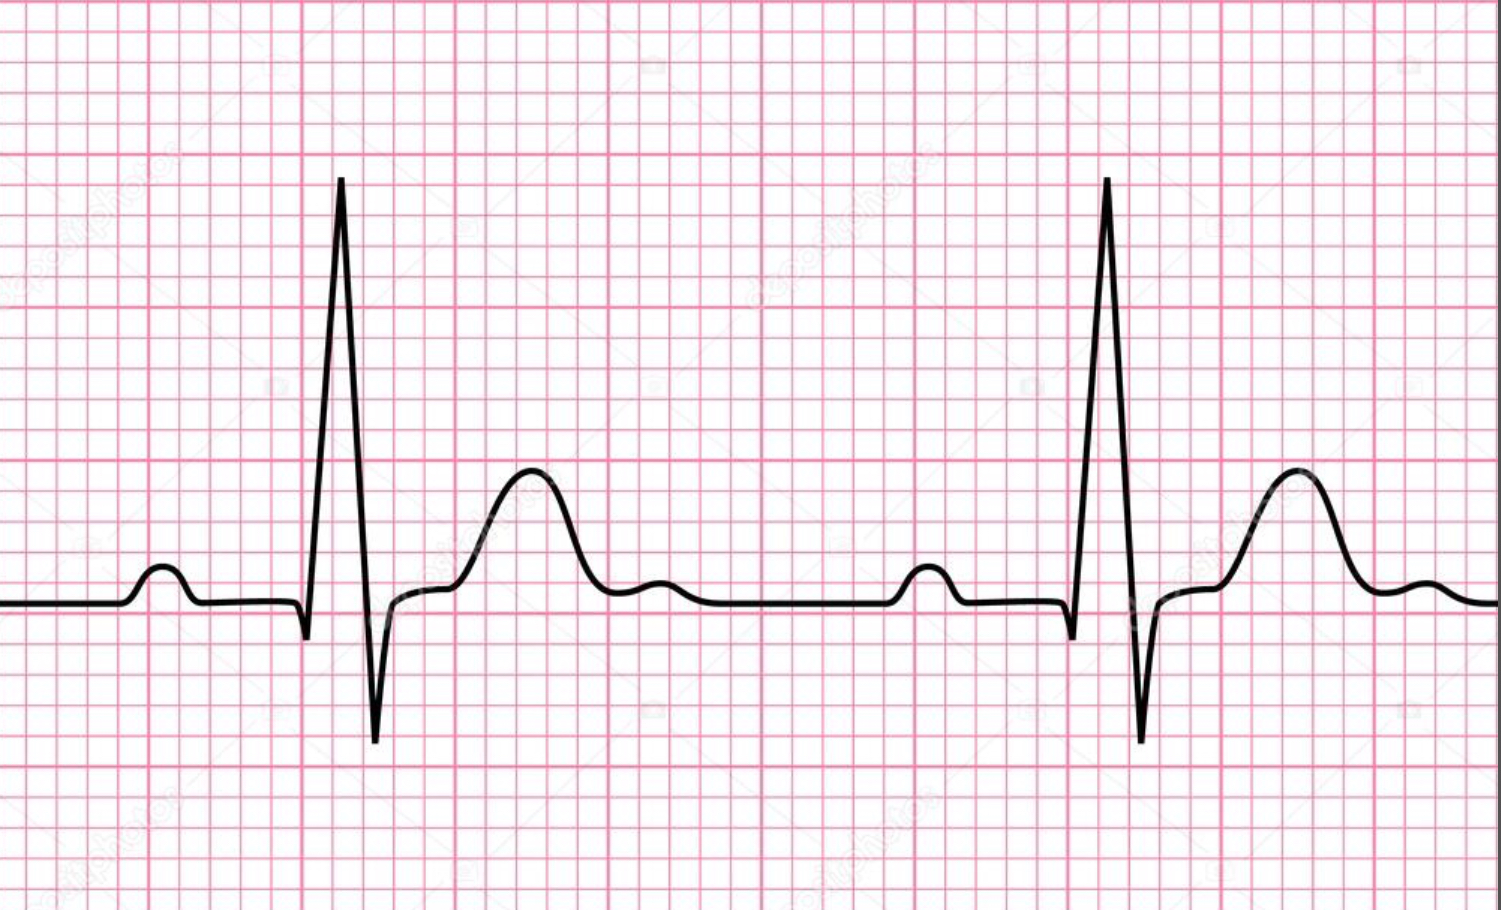

P wave

atrial depolarization

Precedes atrial contraction

QRS complex

ventricular depolarization

Precedes ventricular contraction

T wave

ventricular repolarization

RR interval

Distance from the peak of one R wave to the peak of the next